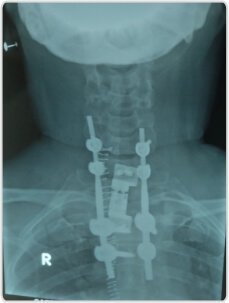

D1, D2 corpectomy with cage fixation and posterior cervico-dorsal stabilization was done by substernal approach for additional support

to prevent implant failure.

Post op X-ray